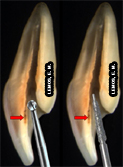

Para a seleção da broca utilizada para a CA devemos levar em consideração o volume da cãmara pulpar, valendo-se da radiografia de diagnóstico, seta amarela: |

| Broqueiro endodôntico para CA e Preparo Cervical | Brocas AR esféricas diamantadas: 1011, 1013 e 1015 - seleção do tamanho | Volume da câmara pulpar |